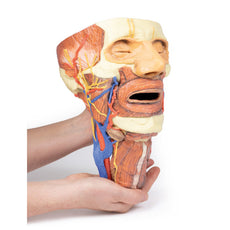

3D Printed Brain Hemisection

This 3D model is a midsagittal hemisection through a whole brain, preserving the right side anatomy and deep brain

structures and spaces visible in the midline. In lateral view, the right cerebral and cerebellar hemispheres are

covered in the arachnoid mater. In the midline view, the brain regions from the cerebrum to the medulla oblongata

are preserved. Centrally, the third ventricle is opened, with an intact septum pellucidum superiorly positioned and

obscuring the lateral ventricles within the cerebral hemisphere. On the inferior margin of the third ventricle both

the right mamillary body and right optic tract can be observed, whereas posteriorly the cerebral aqueduct can be

observed extending across the midbrain between the tectum and tegmentum towards the fourth ventricle (between the

cerebellum and pons). The cerebellum is separated from the occipital lobe by a preserved portion of the tentorium

cerebelli, and in cross-section the cerebellar cortex helps form the prominent arbor vitae.

A series of arterial

branches have been false coloured to contrast their course across the preserved brain structures. In the midsagittal

view the anterior cerebral artery courses from around the corpus callosum to supply the cingulate gyrus and other

midline cortical regions. The base of the middle cerebral artery can be seen passing deep between the temporal and

frontal lobes, with the posterior communicating artery connecting it to a small remnant of the posterior cerebral

artery. Adjacent to the posterior cerebral is the superior cerebellar artery, extending laterally to pass between

the temporal lobe and the cerebellum before passing deep into the transverse fissure.